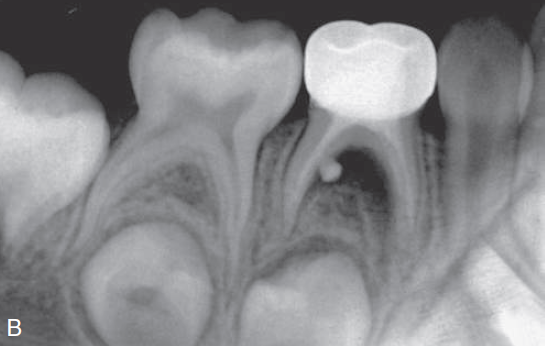

19. (Select ONE correct answer)

What is the most likely diagnosis for the entity shown by the arrow?